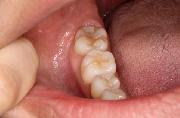

4.次は歯肉(歯ぐき)、口の粘膜です。

しこりや出血はないですか?

5.人差し指で唇を開いて、上と下の歯肉(歯ぐき)、口の粘膜を見ましょう。